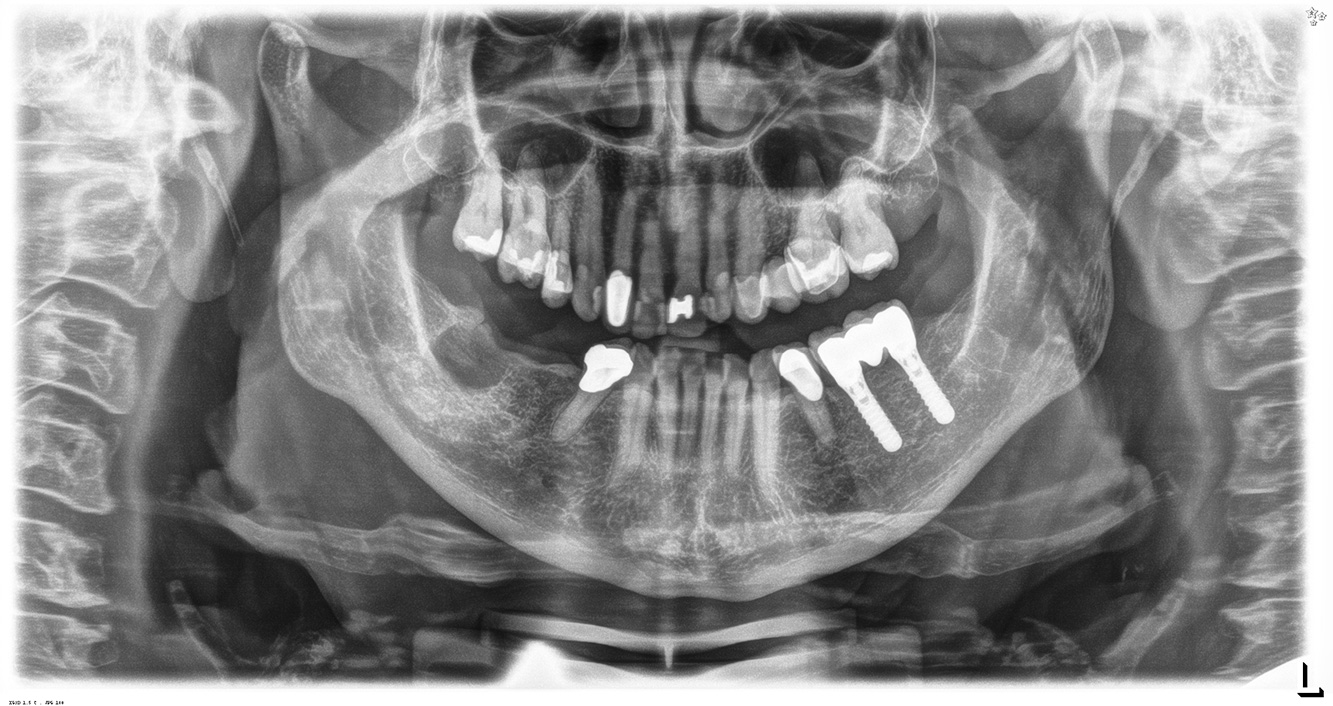

Der (mund)-gesunde Patient mit Implantaten

Der 55-jährige Patient gibt in der Anamnese an, keine Allgemeinerkrankungen zu haben und keine Medikamente einzunehmen. Die Lebensgewohnheiten des Patienten sind ebenfalls unauffällig. Der Patient hat einige zahnärztliche Restaurationen und zwei Implantate (2. und 4. Quadrant). Anhand der aktuellen Befunde lässt sich eine Gingivitis bei stabilem parodontalen Zustand am reduzierten Parodont (Stadium III, Grad A) feststellen. mehr Infos

Der gesunde Patient mit parodontaler Vorerkrankung & Periimplantitis

Ein 52-jähriger Patient stellt sich zur Präventionssitzung vor. Der Patient hat keine Allgemeinerkrankungen und nimmt keine Medikamente ein. Er hat verschiedene zahnärztliche Versorgungen und zudem zwei aktive kariöse Läsionen. Außerdem verfügt der Patient über vier Implantate (2., 3. und 4. Quadrant). Es zeigt sich eine parodontale Vorerkrankung (Stadium IV, Grad B). Derzeit herrschen stabile parodontale Verhältnisse, lediglich am Implantat regio 36 zeigen sich Sondierungstiefen (ST) von 5 mm. Zudem lässt sich eine Gingivitis feststellen. mehr Infos

Die gesunde Patientin mit parodontaler Vorerkrankung

Die 68-jährige Patientin hat keine zahnmedizinisch relevanten allgemeingesundheitlichen Vorerkrankungen oder Medikation, auch aus dem Lebensstil ergibt sich kein besonderes Risiko. Die Patientin hat zwei Implantate (3. Quadrant, seit fünf Jahren) sowie eine parodontale Vorerkrankung (Parodontitis Stadium IV, Grad B) mit Zahnverlust. Derzeit zeigen sich stabile parodontale Verhältnisse. Für die Prophylaxesitzung ergeben sich vier Empfehlungen in den Bereichen Anamnese/Befund, Motivation/Instruktion, der Wahl der geeigneten Instrumente und für Resümee/Folgetermin. mehr Infos

NIWOP – No Implantology without Periodontology